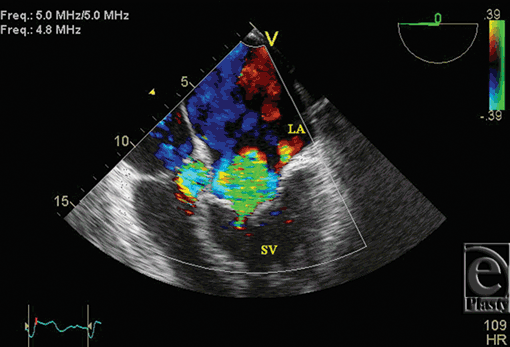

Initial 2D echocardiogram showed severe mitral valve regurgitation with a left ventricular ejection fraction of 35%. Furthermore, the valvular anatomy appeared peculiar; based on right ventricle (RV) and left ventricle morphology, CCTGA was suspected. A transesophageal echocardiography (TEE) was performed for further evaluation. It confirmed our diagnosis of CCTGA. Also, the (TEE) showed a hypertrophied RV and severe systemic AV (SAV) valve regurgitation (Figs 1 and 2). There was no evidence of an atrial septal defect, VSD, or patent ductus arteriosus. An MRI (magnetic resonance imaging) was performed to elucidate the anatomy. It affirmed the diagnosis of CCTGA with a trileaflet SAV that demonstrated severe regurgitation from the systemic ventricle (SV) to left atrium (Figs 3-6). Because of the patient's symptoms and severity of the regurgitation of the SAV, we decided to perform SAV replacement. Preoperative cardiac catheterization showed left dominant coronary circulation with left circumflex and a ramus intermedius originating from left cusp through separate ostia (Figs 7 and 8). Left anterior descending artery originated from proximal right coronary artery through a single ostium from right coronary cusp (Figs 8 and 9). No obstructive coronary heart disease was found and the patient proceeded to surgery.

![]() |

| Figure 2. Transesophageal echocardiogram color Doppler showing severe systemic atrioventricular valve regurgitation. |